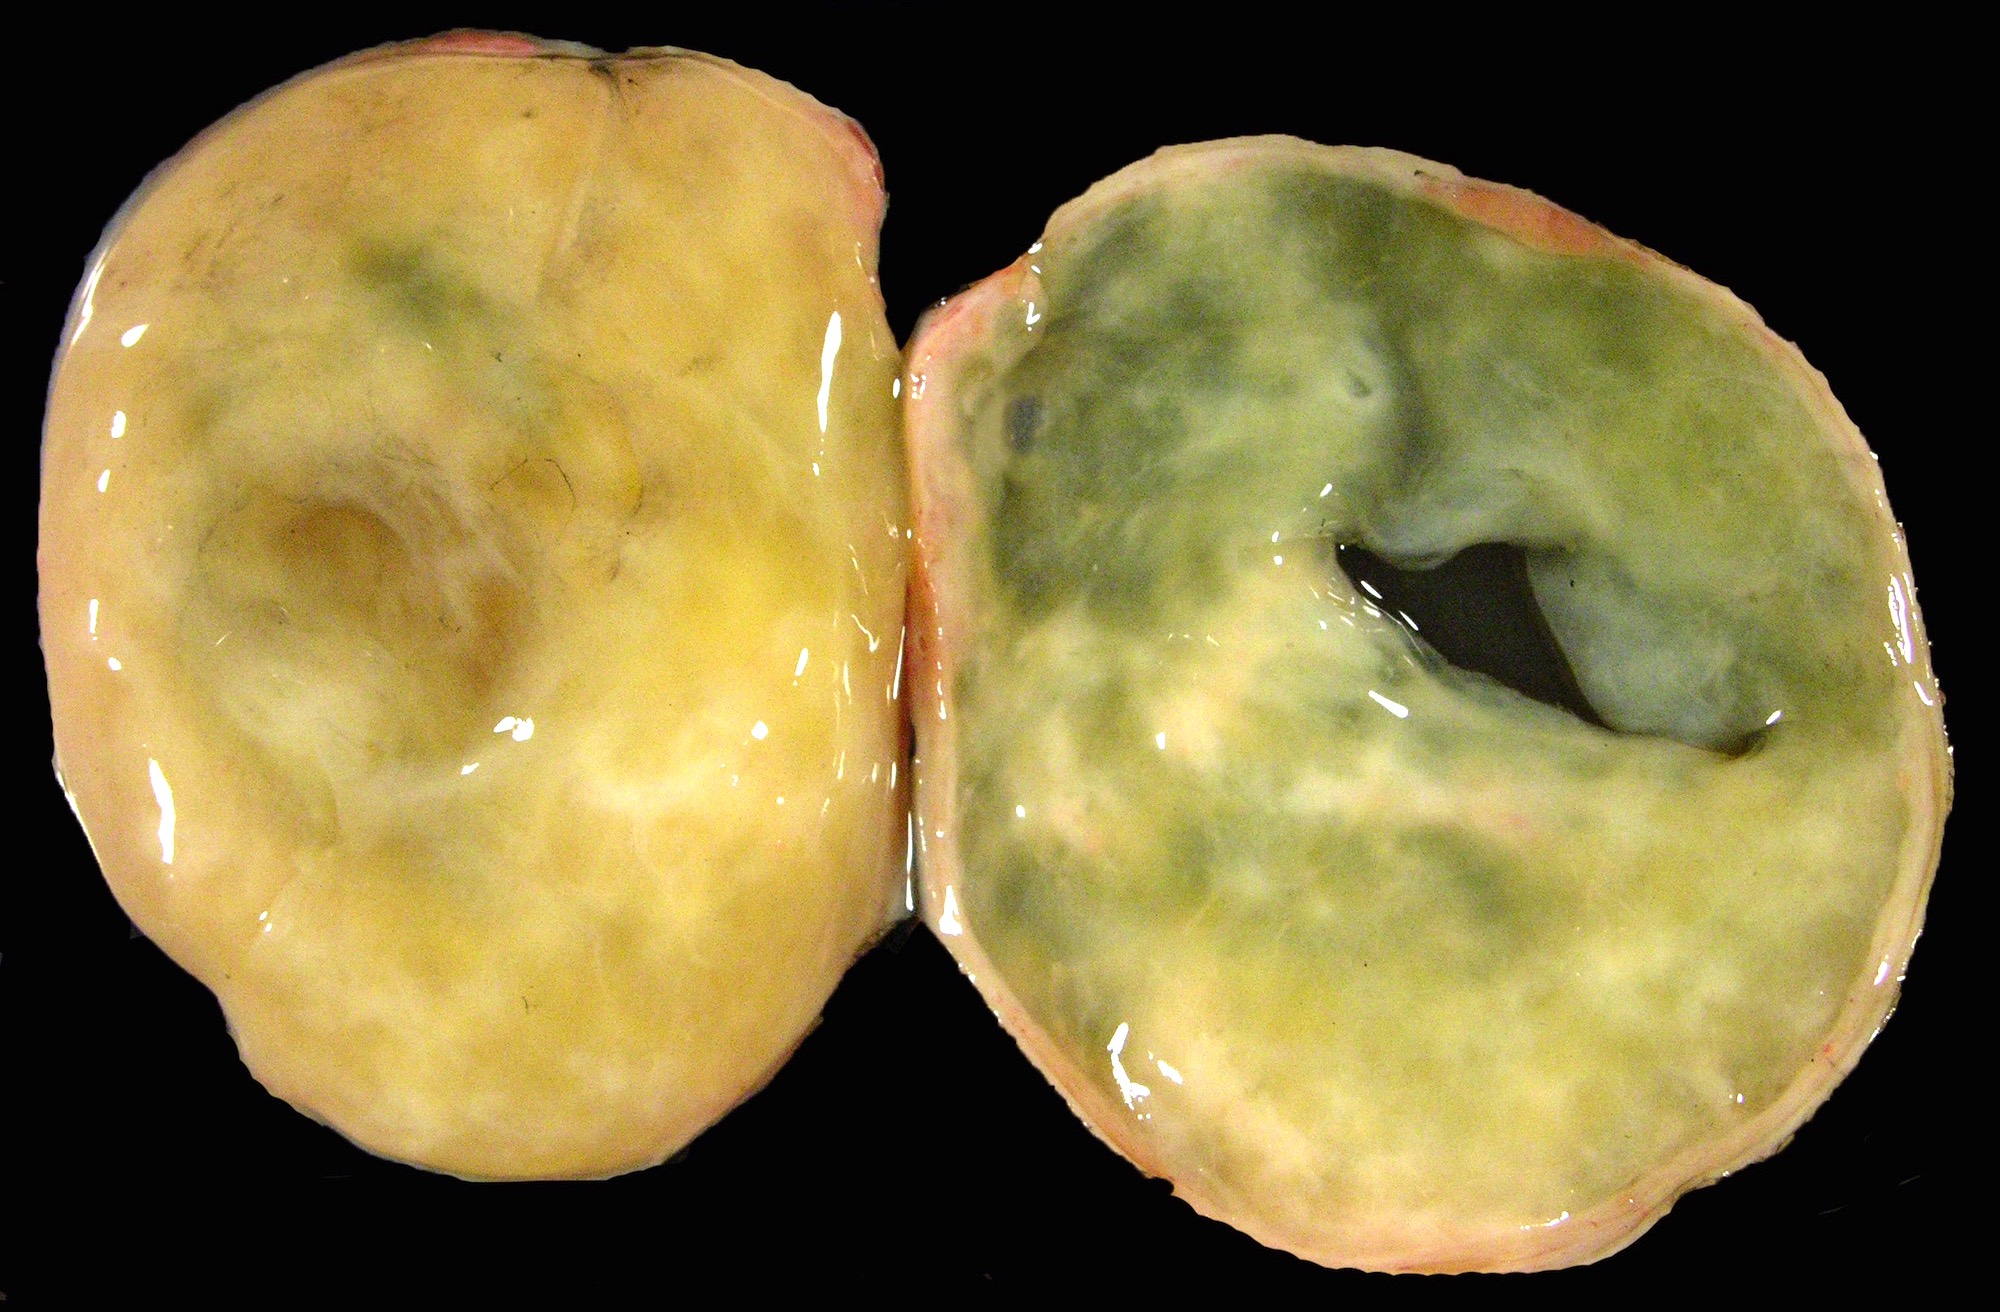

Gross description

- Typically unilateral and well circumscribed, ranging from 1.0 - 23 cm (mean: 8.4 cm) (Histopathology 2022;80:360)

- White-yellow variegated solid mass, often edema and cysts

- Hemorrhage, calcifications and rarely necrosis may be seen